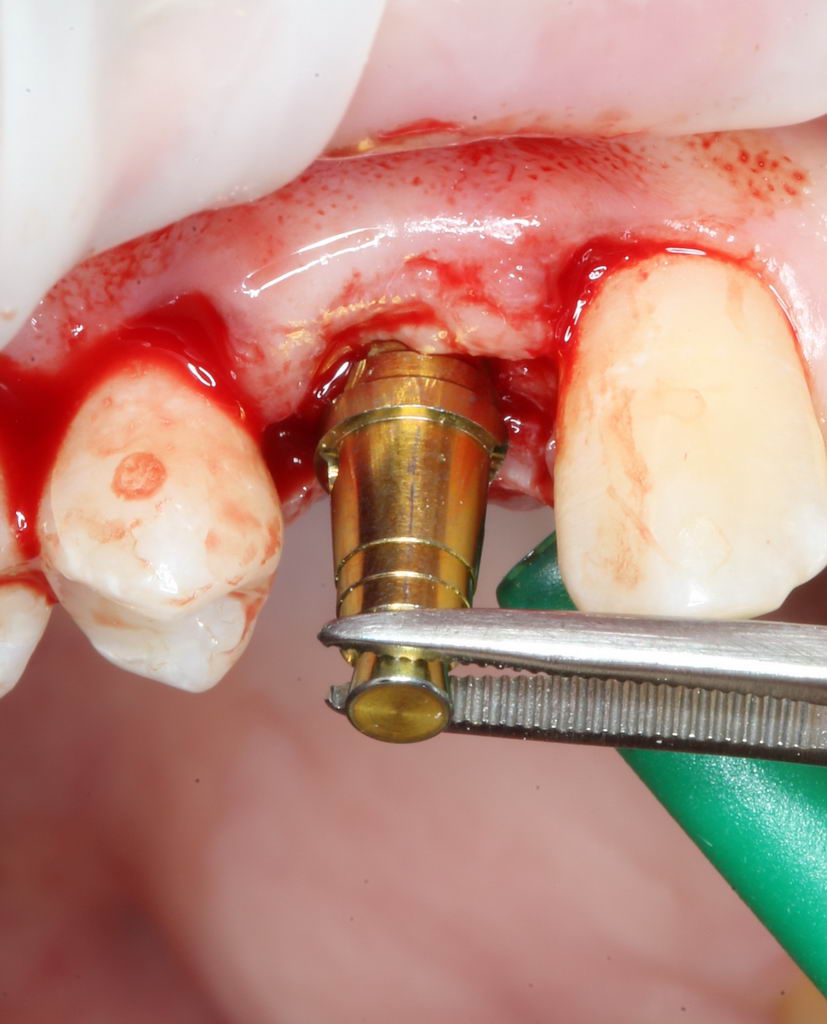

Больше нам абатмент TempBase не нужен, мы его убираем:

Без абатмента можно оценить позиционирование имплантата по глубине погружения. Напомню, что XiVE — это субгингивальная имплантационная система, поэтому ортопедическая платформа имплантата должна находиться на уровне костной ткани. Что и было выполнено в нашем случае.

И, коль всё в порядке, переходим к следующему этапу операции — установке формирователя десны.

Установка формирователя десны.

Одномоментная установка формирователя десны позволяет сократить время и удешевить лечение — ведь по мере интеграции имплантата мы получаем нормально сформированный контур десны, готовый к установке протетической конструкции. Но это возможно лишь тогда, когда с объемами мягких тканей в области имплантата всё в порядке. То есть, как раз в нашем случае.

В CLINIC IN используют только одноразовые формирователи и только один раз:

С учётом клинических условий, мы подобрали к установленному имплантату формирователь Slim (без расширений) высотой 3 мм: